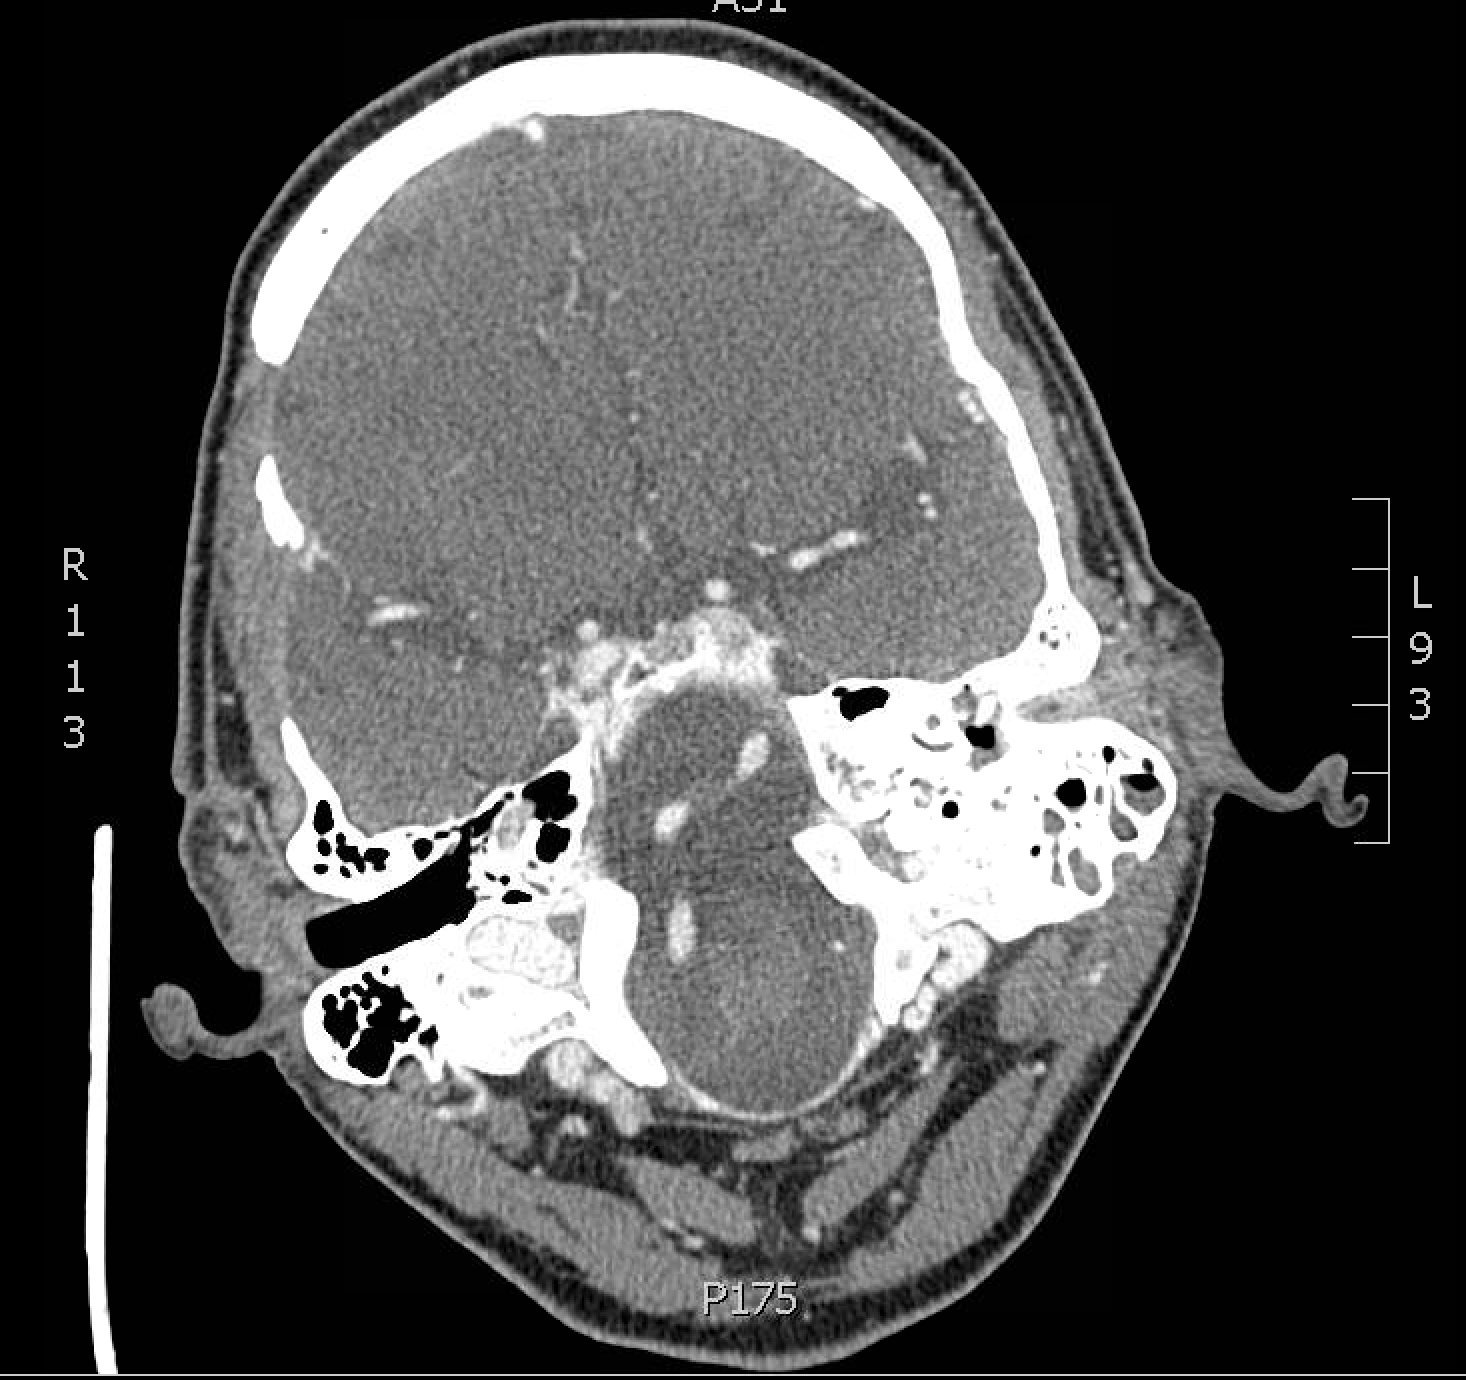

Significant findings:

The patient underwent computed tomography (CT) of the head which revealed opacification of the left middle ear (red arrow) and mastoid air cells (red circles). Additionally, there was thickening of the soft tissues of the external auditory canal (blue arrowhead), likely reflecting concurrent otitis externa.  Based on the imaging, he was admitted for findings consistent with acute otomastoiditis.